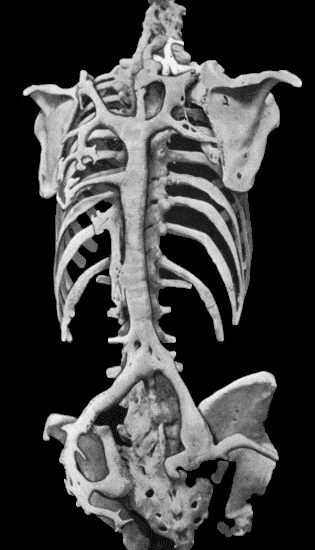

467 133.Skeleton of Rickety Dwarf

470 134.Changes in the Skull resulting from Ostitis Deformans

474 135.Cadaver, illustrating the alterations in the Lower Limbs resulting from Ostitis Deformans

475 136.Osteomyelitis Fibrosa affecting Femora